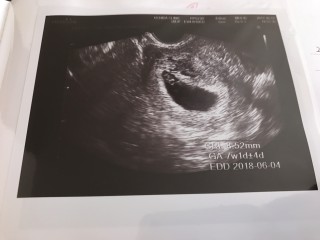

BTで授かっています。前週に胎芽、卵黄嚢、心拍確認。どれだけ大きくなってるかという今回はCRL8.52mmと小さい感じでしたが、特に何も言われないし、心拍もあるし、位置や向きのせいだろうと思うことに。そして翌週には19mmと問題なし。出血もわずかに時々みられていましたが、問題なし。普通に長時間勤務、夜勤もしていました。つわりで辛いので休みの日は何もしていませんでしたが。